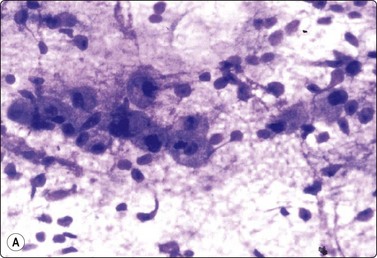

image image

Fig. 4.9 Nasopharyngeal carcinoma (undifferentiated, lymphoepithelial type, WHO type III)

Loose clusters of undifferentiated epithelial cells with vesicular nuclei, prominent nucleoli and pale fragile cytoplasm. Background of lymphocytes. (A, MGG, HP; B, H&E, HP).

Nasopharyngeal carcinoma (NPC) is a clinicopathologic entity different from other squamous cell carcinomata of the head and neck. It is distinguished by its particular histology, geographic distribution, relationship to Epstein-Barr virus, and the absence of an alcohol or tobacco etiological relationship. A proportion of NPCs show squamous differentiation and the cytological pattern of non-keratinizing squamous cell carcinoma (squamous cell carcinoma/WHO type II) (Fig. 4.8). Keratinized cells (WHO type I) are uncommonly found. The majority of NPC are poorly differentiated or undifferentiated. Cells from undifferentiated NPC (UCNT, WHO type III) form loose clusters with no specific microarchitectural pattern, and are usually mixed with lymphoid cells. In the ‘lymphoepitheliomatous’ type (Schmincke-Regaud) the cells tend to be less cohesive, resembling Hodgkin’s disease or large cell non-Hodgkin lymphoma. However, in NPC, the malignant cells are still clustered and have more abundant pale cytoplasm contrasting with the lymphoid cells in the background (Fig. 4.9). Plasma cells are frequently found among the lymphoid cells. Immunostaining for cytokeratin and a pan-lymphocyte marker is helpful. Epstein-Barr virus-associated nuclear antigen is demonstrable by anticomplement immunofluorescence in undifferentiated tumors. Other patterns of growth may occur and may cause diagnostic problems; for example, spindle cell forms may be difficult to recognize as carcinoma.

NPC frequently presents to the cytologist as a lymph node metastasis in the neck without a known primary. Cytological recognition is important since the primary is often clinically occult.